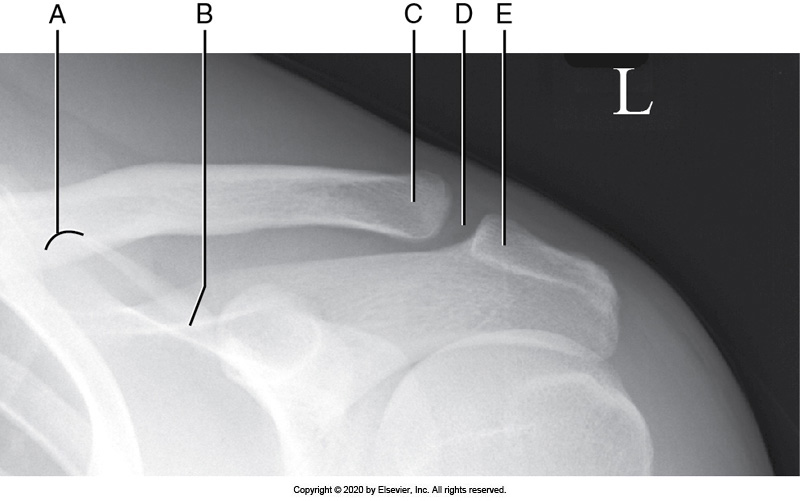

Identify the labeled "I" anatomy in the image below:

Greater tubercle

Coracoid process

Humeral head

Acromion process

Identify the labeled "E" anatomy in the image below:

Scapular body

Superior scapular angle

Identify the labeled "D" anatomy in the image below:

AC joint

Scapular spine

Lateral clavicle

Medial border

Glenoid cavity

Lateral border